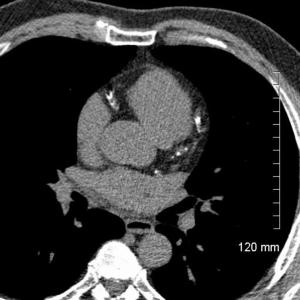

Figure 1. 3-D rendering from a cardiac CT dataset demonstrating mild dilation of the ascending aorta.

Figure 2. CT dataset depicting extensive coronary artery calcification.

Figure 3. Cardiac CT image depicting moderate coronary artery calcification.

The aorta, the largest artery in the body, carries blood from the left ventricle, the heart's main pumping chamber, to the rest of the body. The short section that rises from the left ventricle and supplies the coronary arteries with blood is called the ascending aorta. Enlargement, or dilation, of the ascending aorta can increase the chances of a life-threatening aneurysm. Risk factors for dilation include high blood pressure, smoking and connective tissue disorders.

"Patients whose ascending aortas are more than 4 centimeters in diameter are generally considered to have dilation, which can progress over time and potentially weaken the wall of the aorta," said study author Christopher Maroules, M.D., formerly of the University of Texas Southwestern Medical Center in Dallas and current chief of cardiothoracic imaging at the Naval Medical Center in Portsmouth, Va.

Compared to the control group, former NFL athletes had significantly larger ascending aortic diameters. Almost 30 percent of the former NFL players had an aorta wider than 4 centimeters, compared with only 8.6 percent of the non-players. Even after adjusting for age, body mass and cardiac risk factors, former NFL players were still twice as likely as the control group to have an aorta wider than 4 centimeters.